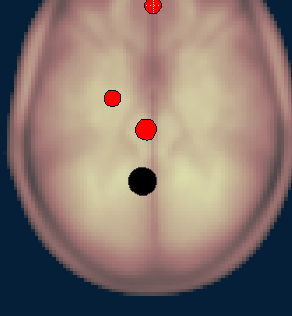

When looking at the PCC ROI, it seems like it is not centered on the midline, rather is almost completely on the left size (and the coordinates give the same location outside CONN, too). I couldn't find any explicit info' about it in the Fox 2005 paper, and wanted to verify that this is indeed the case?